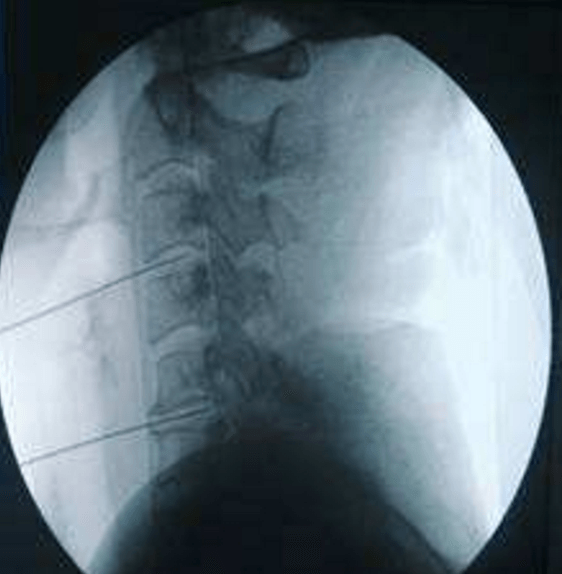

頸、腰椎間盤射頻微創(chuàng)手術(shù)

經(jīng)過多年的發(fā)展,現(xiàn)在的延安大學(xué)咸陽醫(yī)院疼痛科在診療技術(shù)上已經(jīng)達(dá)到一流的水平。尤其在頸、腰椎間盤突出微創(chuàng)治療方面,手術(shù)量居地區(qū)前列,脊柱壓縮骨折椎體成型術(shù)、頸、腰交感神經(jīng)射頻調(diào)控微創(chuàng)手術(shù)、三叉神經(jīng)痛、帶狀皰疹后神經(jīng)痛以及外周血管介入、腫瘤微創(chuàng)介入、內(nèi)臟出血等介入治療方面,為地區(qū)最優(yōu)秀的疼痛科之一。